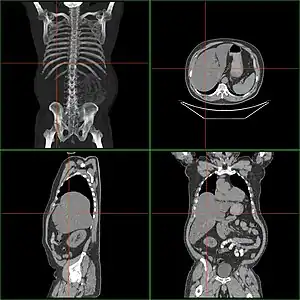

Computed tomography finding of hepatomegaly.

Computerized tomography (CT) can help to obtain accurate anatomical information, in individuals with hepatomegaly for the purpose of a complete diagnosis.[21]